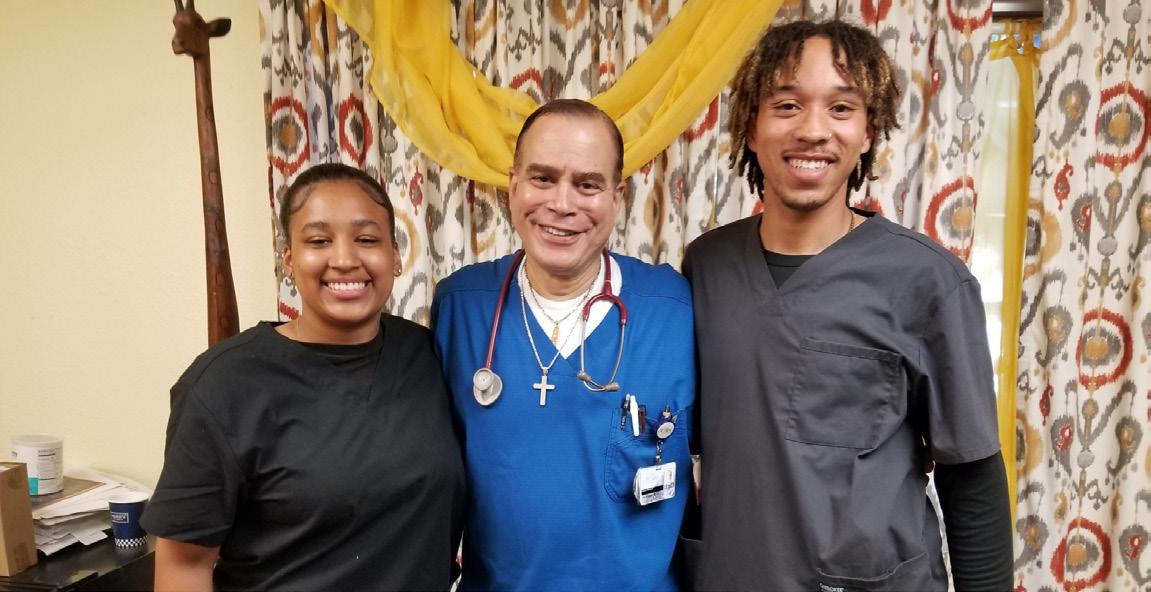

In a May 22 Health Beat TV interview conducted by attorney John Burris, Dr. Geoffrey Watson and Dr. Ralph Peterson were asked, “As African American physicians, do you feel that you’ve been treated differently than Caucasian physicians?”

Health Beat TV show participants left to right are John Burris, Dr. Geoffrey Watson and Dr. Ralph Peterson.

with some of his young medical and health trainees. Continued on page 8 Continued on page 8 Continued on page 8 Continued on page 8

Dr. Watson